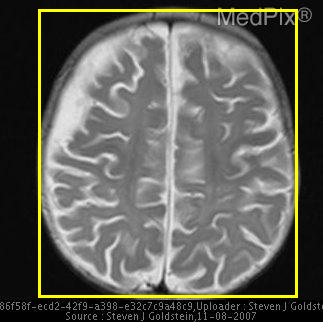

Refer to caption

Figure 1: Overview of MedVistaGym, which contains a comprehensive suite of reasoning-intensive medical image analysis tasks and tools in an interactive execution environment, scaling visual-centric tool-integrated agentic reinforcement learning for VLM agents.